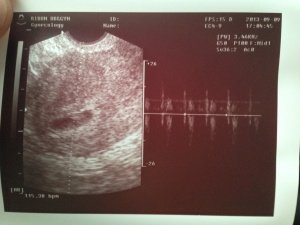

여기 집안에 하얀거 보이세요 아가에요 잘크고 있네요 ~ 자 심장소리 들어볼까요?

쿵쾅 쿵쾅 아직 초기라 작지만 잘 들리죠? 6주 ~ 신기 방기 울컥 울컥

신랑도 신기방기 ~